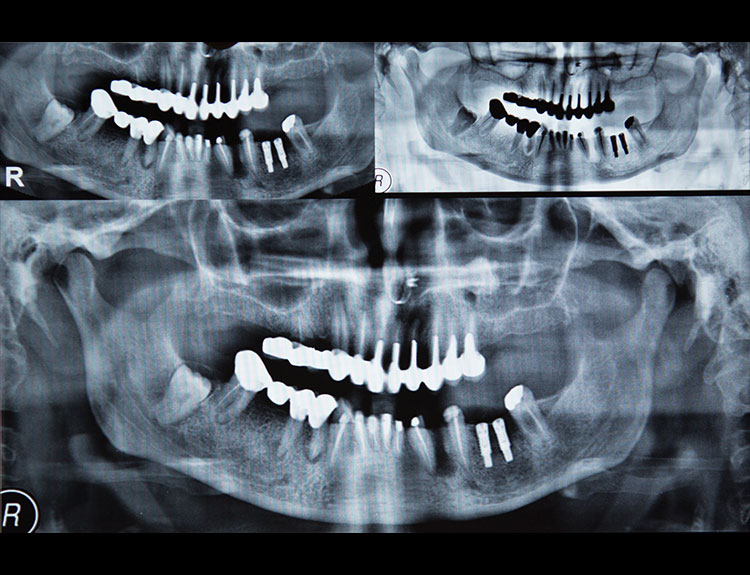

Dental implants are artificial tooth roots made of medical-grade titanium that are surgically placed into the jawbone. Once the implant integrates with the bone, a crown is fixed on top, giving you a strong, natural-looking replacement tooth.